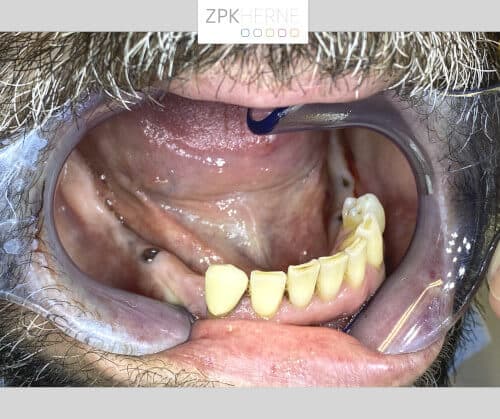

Über ein Jahrzehnt lang hat die Furcht vor dem Behandlungsstuhl unseren Patienten von dem dringend notwendigen Zahnarztbesuch abgehalten. Dabei leidet er fast schon ebenso lange unter einem nicht voll funktionsfähigen Gebiss: Seit mehreren Jahren fehlen ihm im Unter- sowie im Oberkiefer jeweils ab dem Eckzahn einige Zähne. Außerdem ist die Bisshöhe abgesackt, das heißt seit Jahrzehnten knirscht sich der Patient die Zahnsubstanz herunter. Das führt unter anderem dazu, dass er nicht mehr vernünftig essen kann. Hierfür wünscht er sich eine neue festsitzende Versorgung mittels Implantate.

Nach der gründlichen Anamnese werden aktuelle 3D-Aufnahmen der Gebisssituation erstellt. Dabei kommt das Team um Herrn Dr. Mintert zu den folgenden Ergebnissen und Handlungsschritten: